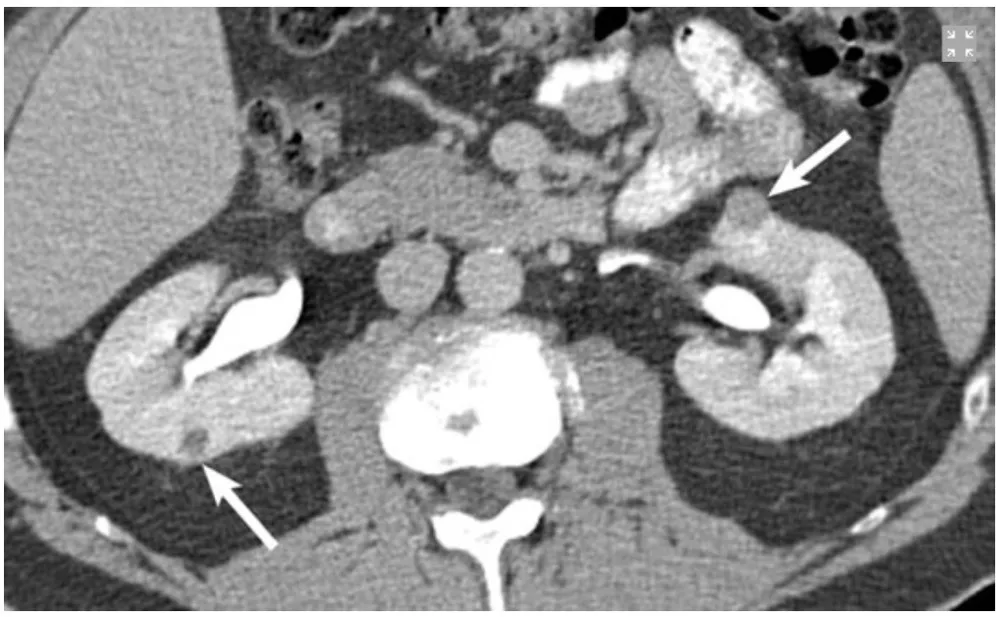

Múltiplos tumores renais